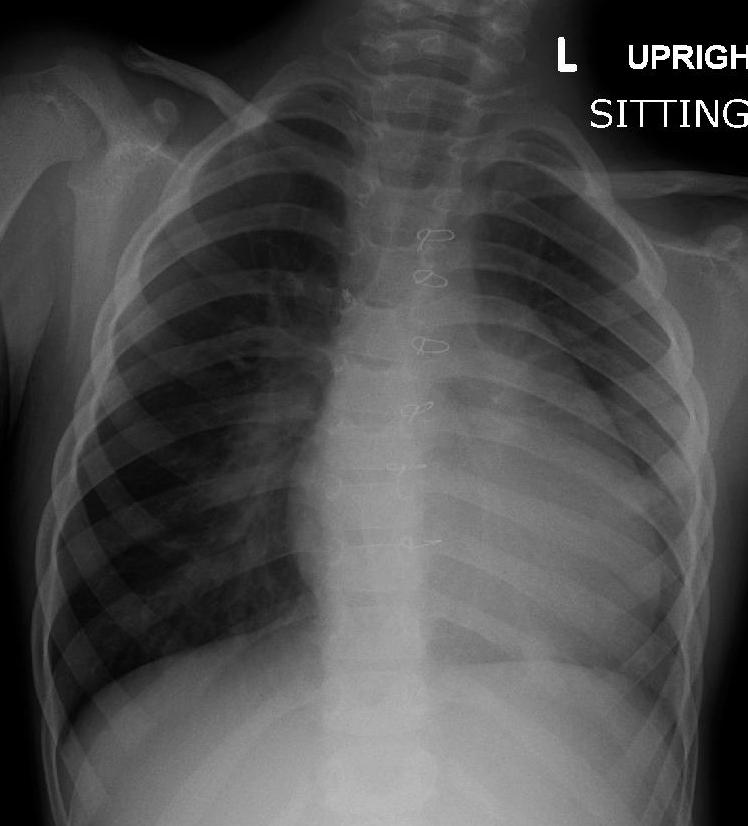

Coarctation of the Aorta

Coarctation of the aorta results in an abnormal narrowed portion of the aorta.

Coarctation of the aorta is separated into juvenile and adult versions.

Juvenile version of coarctation of the aorta

A patent ductus arteriosus (PDA), infantile form is connected.

Coarctation is located distal (after) to the aortic arch and proximally (before) to the patent ductus arteriosus (PDA).

Coarctation of the aorta presents in babies as lower extremity cyanosis, mostly after birth.

Coarctation of the aorta is linked to Turner syndrome (monosomy X).

Adult version of coarctation of the aorta

A patent ductus arteriosus (PDA) is not connected to adult form of coartctation of the aorta.

After (distal to) the aortic arch is where the coarctation is typically located in adults.

Coarctation of the aorta in adults typically presents with:

- Hypertension in the upper extremities

- Hypotension with weak pulses in the lower limbs

Radiology of coarctation of the aorta classically shows “notched ribs” on an x-ray due to collateral vessels.

Coarctation of the aorta is linked with the bicuspid aortic valve.